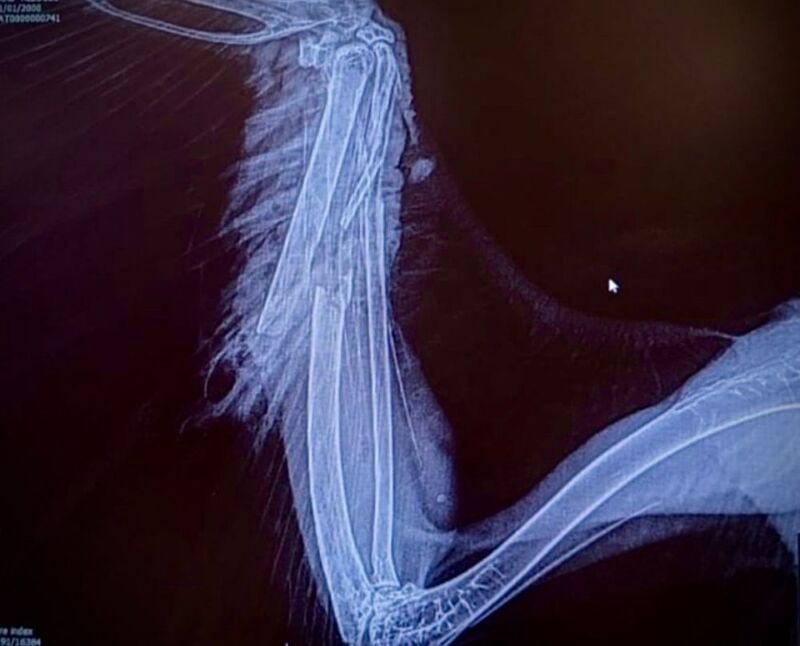

Rocco è stato trovato ferito vicino a Bressanone e presentava una complessa frattura al radio e all’ulna. Il dottor Stefano Capodanno, membro dell’equipe, ha dettagliato il processo di recupero: “Dopo una prima fase di stabilizzazione con antidolorifici e antiinfiammatori, e l’avvio di una terapia antibiotica per le lesioni ai tessuti molli, abbiamo proceduto all’intervento chirurgico con l’inserimento di un chiodo centro midollare per allineare i monconi ossei.”